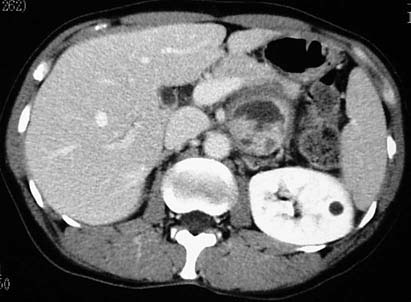

CaseFR01

- Age/Sex: 47F

- Chief Complaint: 後腹膜腫瘍の全身検索

- Clinical

Course: 約10ヶ月間心窩部痛を繰り返し,腹部CTで左後腹膜腫瘤が指摘された.手術で平滑筋肉腫の診断を得たが,骨シンチグラフィ異常を認めた.

- Lab. Data: BUN 8.1,Cr 0.61,Ca 8.1,Pi 2.8,CEA 正常,CA19-9

正常

- Images:

- X-CT, abdomen